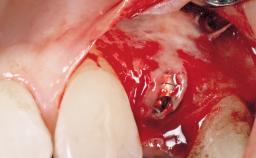

Late Placement of an Implant in a Maxillary Left Central Incisor Site

A 30-year-old female patient had lost tooth 21 and was referred to our clinic for consultation and treatment. Due to advanced apical infection, tooth 21 had been extracted two months earlier at another clinic and an acrylic-resin tooth had been bonded to the adjacent teeth. The patient desired implant treatment to avoid any damage to the adjacent natural teeth. While the patient had no history of any systemic disorder, she was a heavy smoker and exhibited medium to advanced periodontitis in the entire jaw. After the initial treatment to achieve a pocket probing depth of less than 4 mm and no bleeding on probing, a decrease in the height of the papillae mesial and distal to the extraction site and overall gingival recession were observed.

Bone Augmentation | Horizontal|Staged |

Augmentation Materials | Autogenous chips|Membrane |